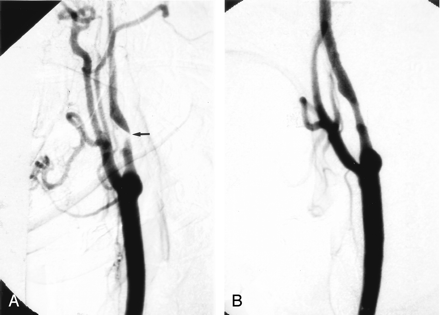

Eleven patients had repeat sonography during the first week after treatment. The mean peak systolic velocity (PSV) fell from 461 cm/s to 275 cm/s and the average ICA/CCA ratio from 7.3 to 3.4. Subsequent follow-up was done in 20 patients, excluding the patient in whom balloon predilatation was required. Follow-up ranged from 1 to 44 months, with an average of 20 months (Figs 4 and 5). Mean PSV at last follow-up in all patients was 164 cm/s (median, 118 cm/s; range, 60–628 cm/s). Mean follow-up ICA/CCA ratio was 2.2 (median, 1.7; range, 0.8–7.9). All had velocities at or below 180 cm/s, except for three patients. One of these three had contralateral ICA occlusion, which would elevate velocities due to increased collateral flow, and this was confirmed by color Doppler, which showed that the degree of stenosis was mild. The second patient had a transient ischemic attack with recurrent severe stenosis at 16 months and continues to be followed. The third patient, by far the worst result in the series, had an unusually marked degree of plaque calcification. Her velocities and ratios remained high—628 cm/s and 7.9, respectively—out to 1 year of follow-up. The degree of plaque calcification prevented stent expansion (Fig 6). She remained free of further episodes of ischemia for 1.5 years, at which time her stenosis progressed to complete angiographic occlusion, with no new evidence of stroke on MR imaging.

A, Right lateral CCA DSA, showing a severe stenosis of the proximal ICA, measuring approximately 80%.

B, Repeat lateral DSA, poststenting alone, showing reduction of the stenosis to approximately 63%.

C, D, and E, Conventional AP radiographs of the neck immediately poststenting (C), 5 months (D), and 8 months (E) poststenting. There has been no further expansion of the stent over 8 months. Note the prominent, focal plaque calcification (arrows).